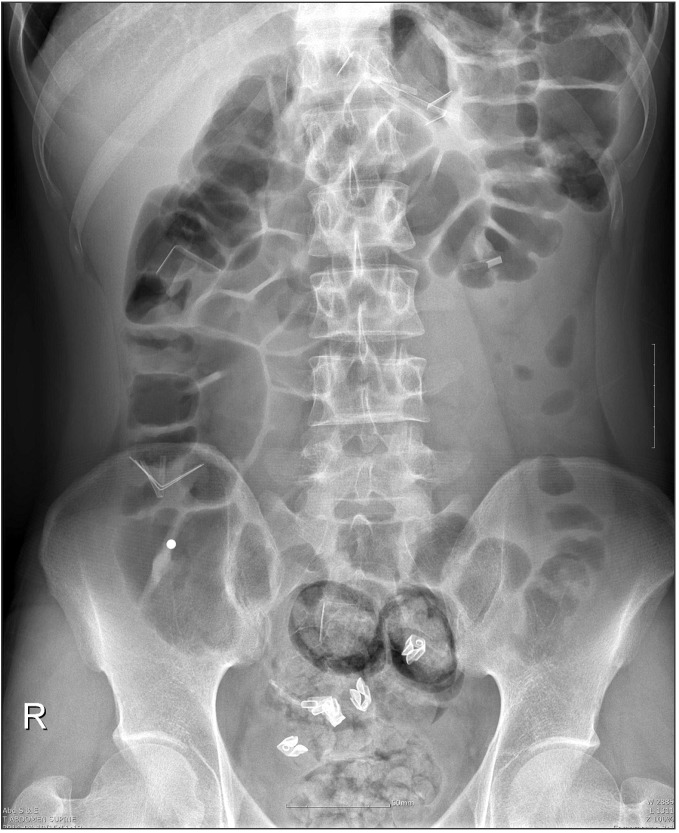

A 22-year-old soldier who has histories of conversion disorder and small bowel segmental resection due to incarcerated inguinal hernia was admitted with a small quantity of hematemesis and epigastric pain. The patient visited military hospital near his unit, and abdomen plain x-ray was performed that showed several pieces of foreign bodies (Fig. 1). But, the patient could not remember the fact of the foreign body ingestion. Then the patient was transferred to The Armed Forces Capital Hospital for further treatment. On physical examination, mild tenderness was found on deep palpation of only epigastric area and rebound tenderness was not present on whole abdomen. The patient did not have a fever. Laboratory test revealed WBCs were 8,440 × 103/µL, Hemoglobin were 16.0 g/dL and other tests were all normal. Abdominal CT showed multiple scattered metal fragments in stomach, appendix, ascending colon, and sigmoid colon without evidences of perforation (Fig. 2). We performed emergent endoscopy and successfully removed four pieces of white plastic fragments, five pieces of metal fragments, and one piece of small black plastic fragment in the stomach body and prepyloric area. Also, we removed a white and black plastic fragment in the duodenum (Fig. 3). Esophagogastroduodenoscopy showed multiple erosions in the esophagus, stomach, and duodenum without perforation and active bleeding. We observed the patient closely and expected other foreign bodies passed through gastrointestinal tract spontaneously. Only one metallic round foreign body in the right lower quadrant was found upon serial abdomen plain x-ray at hospital day 5. Mild right lower quadrant pain started to present at hospital day 16. This pain aggravated at hospital day 17 and physical examination showed mild right lower quadrant tenderness and rebound tenderness. Abdominal CT was taken at hospital day 17 showed a remained round foreign body in appendix, dilated appendix (approximately 7.5 mm in diameter), and wall thickening of appendix midportion (Fig. 4). According to patient's clinical symptoms, signs, and CT, we decided to perform an appendectomy. Due to the patient's abdominal operation history, we performed an open appendectomy at hospital day 17. Operation findings revealed a mild dilated appendix (7 mm in diameter), mild redness around midportion of appendix and a round shaped metallic foreign body in appendix (Fig. 5). According to these findings, we could consider early appendicitis clinically. There were no postoperative complications and the patient was discharged 21 days after surgery. Pathologic evaluation was reported as a 12-cm-long and 0.7-cm-wide macroscopically, subserosal congestion with inflammation microscopically.

Fig. 1. Abdomen plain x-ray reveals several pieces of foreign bodies.